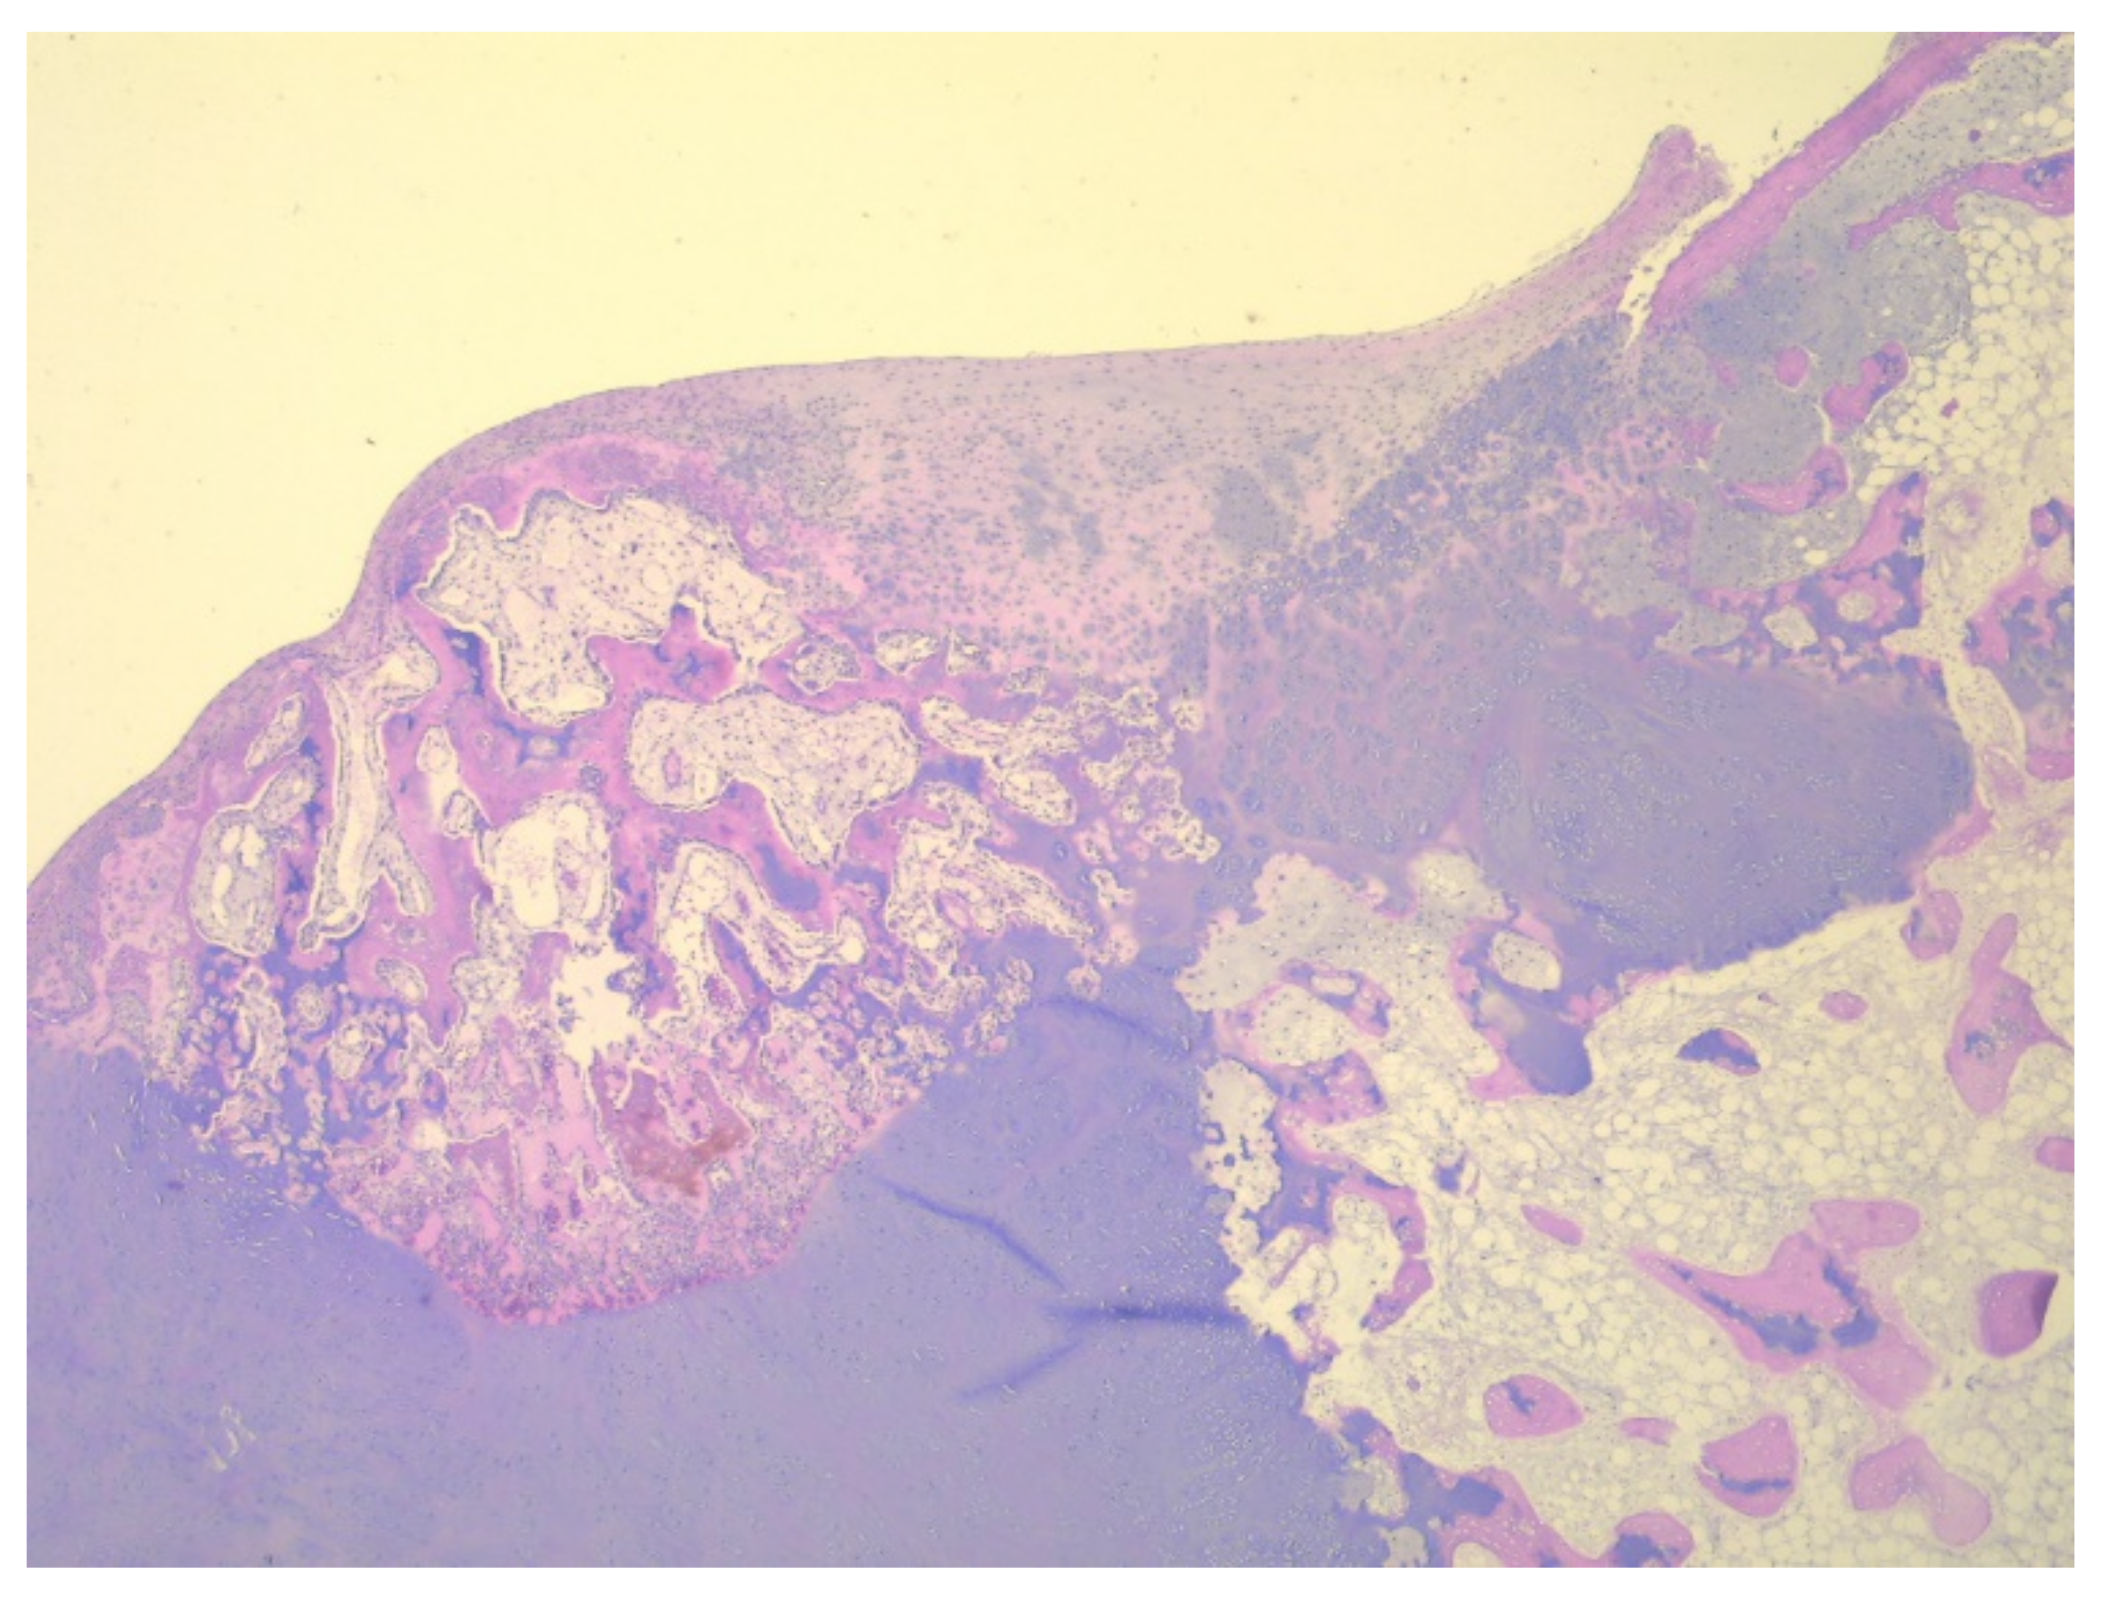

A total of eight tissue fragments, between 0.5 and 3 cm in diameter, were sent for anatomopathological diagnosis. The macroscopic appearance of the tumoral fragments was a nodular polylobate solid mass. On the slide, the top of the tumor was covered by a blue-like cartilaginous cap about 0.1–0.6 cm in width. After decalcification and preparation of formalin-fixed paraffin-embedded tissue blocks the specimen was evaluated. The result indicated tissue fragments made of bone, showing chondroid proliferation on the surface, with minimal cellular atypia, with disorganized distribution and limited columnar pattern at the basal level, slightly increased cellular density, and endochondral ossification with mineralization areas (Figure 9, Figure 10, Figure 11 and Figure 12). Fibroconnective tissue was observed on the surface of chondroid proliferation (perichondrium). The result was indicative for a benign osteochondromatous structure displaying clusters of proliferative chondrocytes in a fibrillary matrix with small ossification centers and small amounts of unabsorbed calcified cartilage. Trabecular bone was covered by an irregular cartilaginous cap.

Figure 9. Irregular and disorganized clusters of mature chondrocytes, HE, 50×.

Figure 10. (A) Disorganized cell clusters with mild cytologic atypia; (B) Areas of cartilaginous tissue undergoing endochondral ossification in to the subjacent trabecular bone, HE, 200×.